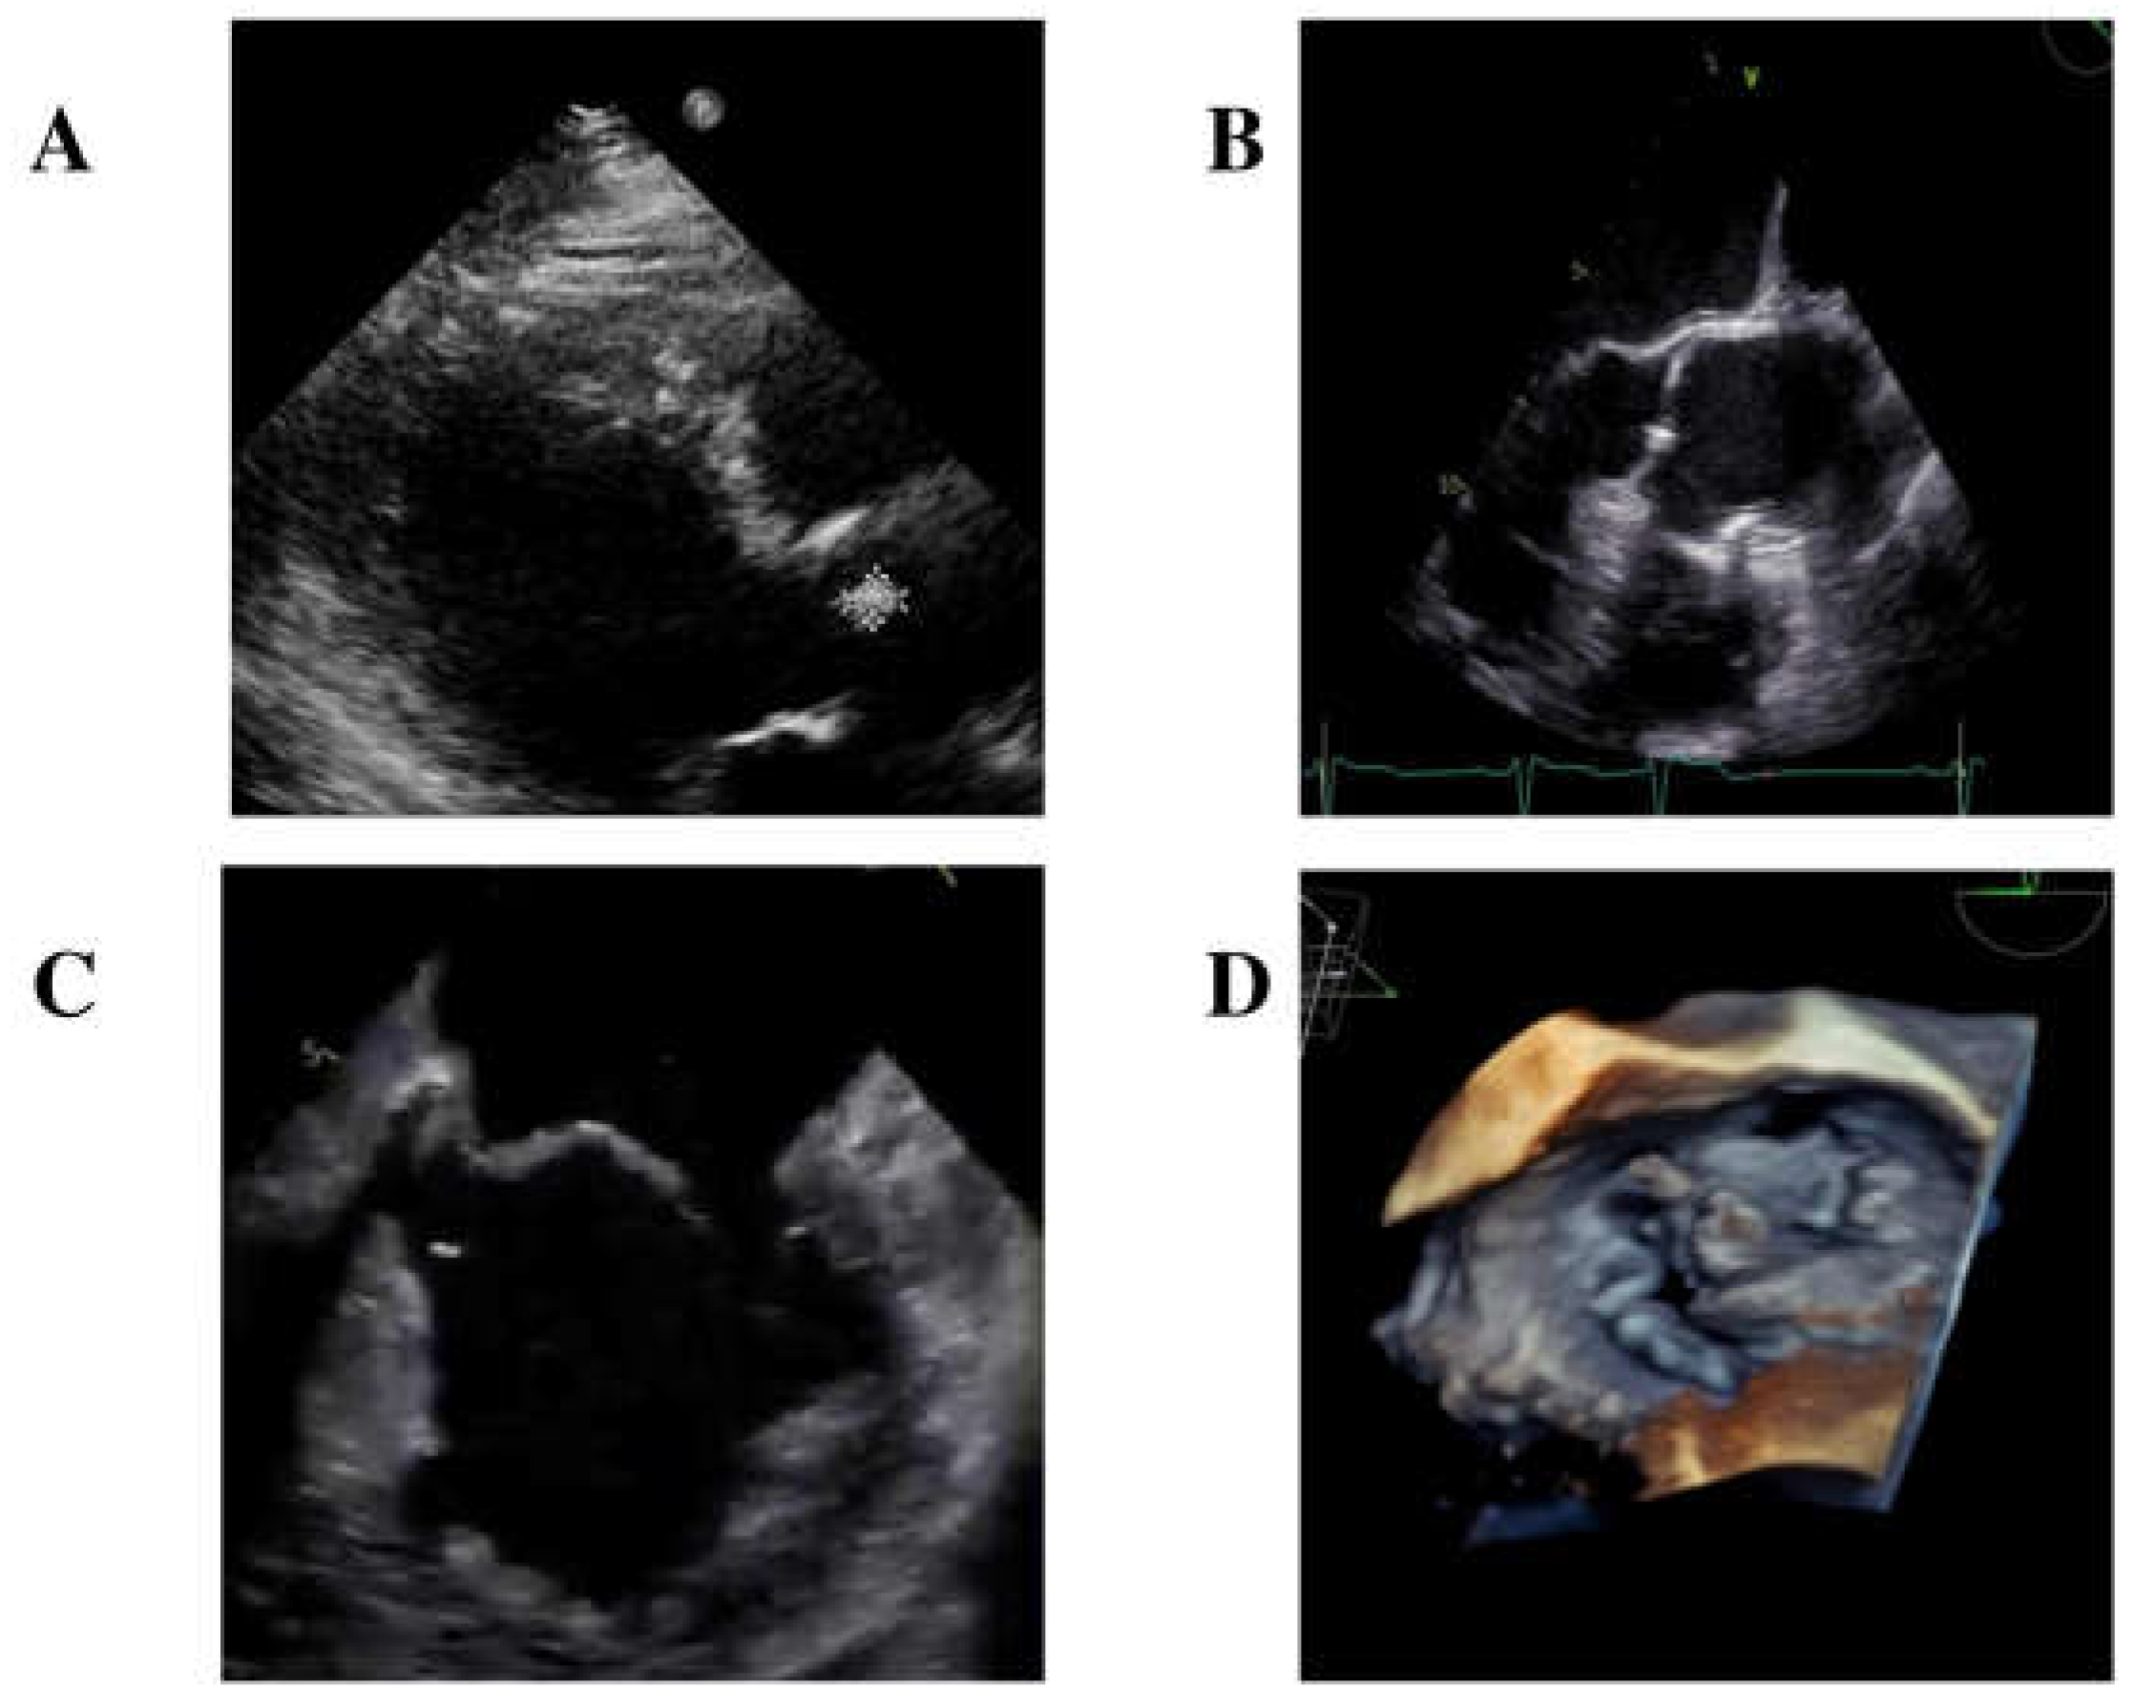

A transthoracic echocardiogram identified a small isoechoic mass (0.7 mm × 10 mm) on the right cusp of the aortic valve (Figure 1A) and diagnosed mitral valve dysfunction with severe regurgitation, requiring the initiation of diuretic therapy.

Furthermore, an empiric antibiotic treatment with intravenous ceftriaxone 2 gr/day was started. In the meanwhile, blood cultures came back positive for Gram-positive rods, and MALDI-TOF identified S. sinensis. Further diagnostic evaluations included a transesophageal echocardiogram (TEE), which confirmed the presence of the isoechoic mass measuring 0.7 mm × 0.7 mm on the right cusp of the aortic valve (Figure 1B). Additionally, TEE identified another long (length = 12.5 mm) mobile iso-echogenic mass on the medial scallop of the posterior mitral leaflet (P2), with a flail of P2 due to rupture of the chordae tendineae (Figure 1C,D).

Figure 1. Transthoracic echocardiogram showing a mobile isoechoic formation at the right cuspid of the aortic valve (A). Transoesophageal echocardiogram image depicting a mobile isoechoic formation measuring 0.7 mm × 0.7 mm on the right cusp of the aortic valve (B); a mobile isoechoic formation on the posterior mitral leaflet with fragmentary flail of P2 due to rupture of the chordae tendineae (C); three-dimensional imaging of the mitral valve with the mass seen on P2 scallop (D).